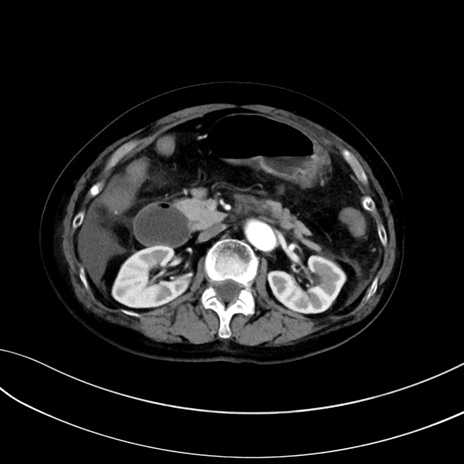

(冠状断像)1日半後